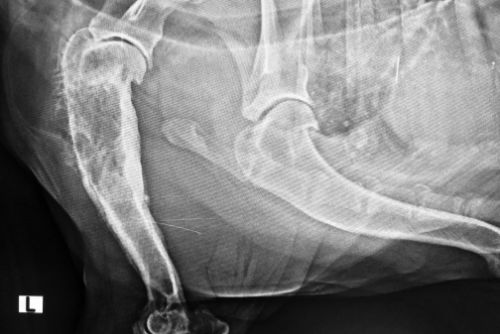

- Osteosarcoma – A highly aggressive form of bone cancer.

Osteosarcoma and Growth Hormones

Large and giant breeds that experience rapid growth in their early years may be at a higher risk of developing osteosarcoma.

Growth hormones and rapid bone development are thought to contribute to this aggressive cancer.

- Lameness or swelling in the limbs

Your vet may recommend biopsies, X-rays, ultrasounds, or blood tests to diagnose potential cancer.